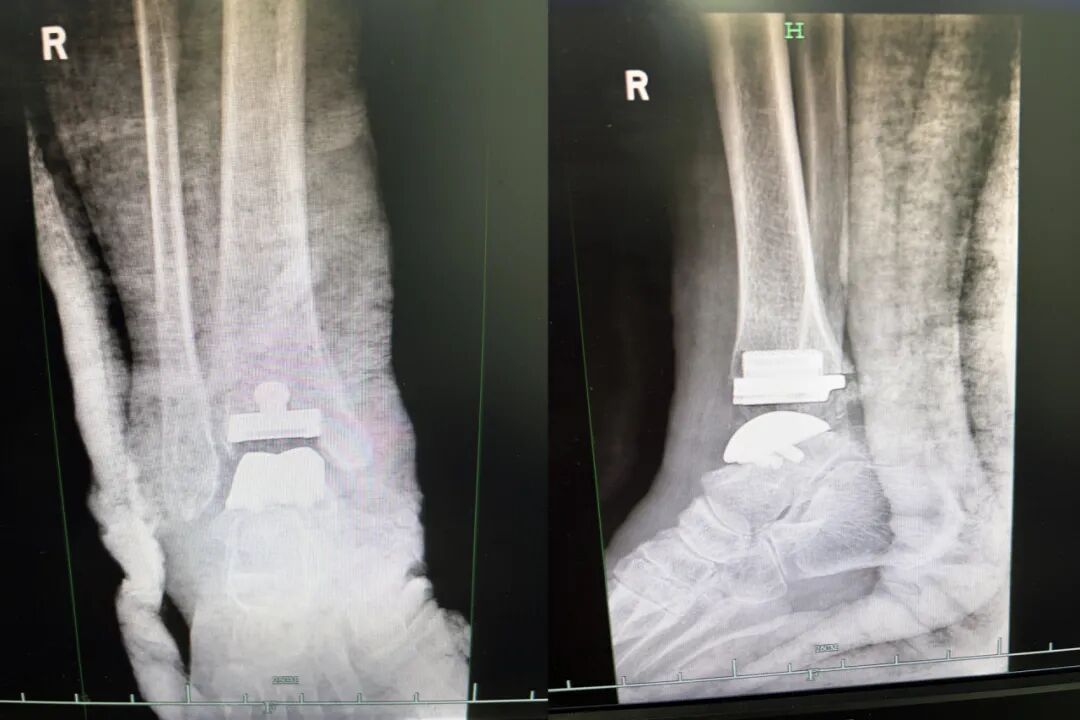

术中,陈红卫主任医师团队按照术前计划精准实施,依据预先设计好的导板精准且迅速地完成截骨和假体植入,手术时间较传统踝关节融合术和骨水泥关节置换术明显缩短。术中及术后影像显示,踝关节假体力线良好,大小合适,胫距关节假体配合良好,踝关节活动满意。

▲ 术后X影像提示人工踝关节假体大小和对合良好,下肢力线良好

“过去的人工全踝关节置换术,医生在术中需要利用X线来多次定位、校准,也依赖于术者丰富的手术经验。”何凌峰表示,3D打印辅助下的踝关节置换术带来的毫米级手术精度,突破了传统的治疗局限,也让患者获益最大